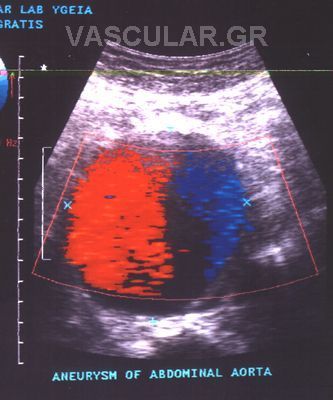

ÓõíÞèùò ç äéÜãíùóç ôïõ áíåõñýóìáôïò ãßíåôáé ôõ÷áßá ìåôÜ áðü êÜðïéá äéáãíùóôéêÞ åîÝôáóç üðùò áêôéíïãñáößá óôçí êïéëéÜ, áîïíéêÞ Þ ìáãíçôéêÞ ôïìïãñáößá êïéëßáò êáé êõñßùò áðü õðåñç÷ïãñÜöçìá Triplex , åéäéêüôåñá äå ìåôÜ áðü áããåéïãñáößá Þ õðåñç÷çôéêÞ ðáíáñôçñéïãñáößá.

2. Ç åíäáããåéáêÞ áíôéìåôþðéóç êáôÜ ôçí ïðïßá ôïðïèåôåßôáé áðü ôçí ìçñéáßá áñôçñßá åíôüò ôïõ áõëïý ôïõ áíåõñýóìáôïò , åíäáõëéêüò íÜñèçêáò (stent) åðåíäåäõìÝíïò ìå åéäéêü õëéêü ãéá áðïêëåéóìü ôïõ áíåõñýóìáôïò.

Ç ôå÷íéêÞ áõôÞ åéóÞ÷èç êáé Ýãéíå ãéá ðñþôç öïñÜ óôçí ÅëëÜäá óôï íïóïêïìåßï «YÃEIA» áñ÷Ýò ôïõ 1995 áðü ôçí ïìÜäá åíäáããåéáêÞò ÷åéñïõñãéêÞò (Ð.ÌðÜëáò, Í.ÐáãêñÜôçò) êáé åîáêïëïõèåß íá ãßíåôáé ìå Üñéóôá áðïôåëÝóìáôá.

H äéÜñêåéá ôçò åðÝìâáóçò åßíáé 100 +- 30 ëåðôÜ êáé ï ÷ñüíïò ðáñáìïíÞò óôï íïóïêïìåßï åßíáé 3-4 çìÝñåò .

Ç áíôéìåôþðéóç ôïõ áíåõñýóìáôïò êïéëéáêÞò áïñôÞò äé åíäáããåéáêÞò ÷åéñïõñãéêÞò áðïôåëåß ìÝèïäï ãéá åðéëåãìÝíïõò áóèåíåßò , áóèåíåßò õøçëïý êéíäýíïõ êáé ðïõ äåí èá çäýíáíôï íá ÷åéñïõñãçèïýí ìå ôçí êëáóéêÞ ìÝèïäï .

Åí ôïýôïéò ìå ôçí áðïêôçèåßóá äéåèíÞ êáé çìåôÝñá åìðåéñßá ïé åíäåßîåéò åêôÝëåóçò ôçò íÝáò áõôÞò ìåèüäïõ äéåõñýíïíôáé þóôå íá ðåñéëáìâÜíåé áóèåíåßò íåùôÝñáò çëéêßáò êáé óå êáëÞ ãåíéêÞ êáôÜóôáóç.

Ïé ÅíäáããåéáêÝò åðåìâÜóåéò óå áíåýñõóìá ôçò êïéëéáêÞò áïñôÞò (ÁÊÁ) õðåñôåñïýí ôçò êëáóóéêÞò åã÷åéñÞóåùò êáè üóïí ãßíåôáé äé åëá÷ßóôïõ ôñáýìáôïò, ç ðáñáìïíÞ ôïõ áóèåíïýò óôï íïóïêïìåßï åßíáé âñá÷åßá, áðïöåýãïíôáé ïé óåîïõáëéêÝò äéáôáñá÷Ýò óå Üíäñåò êáé ç åðÜíïäïò óôéò êáèçìåñéíÝò åíáó÷ïëßåò åßíáé ôá÷ýôáôç.

Ç éäÝá ôçò áðïêáôÜóôáóçò ôïõ áíåõñýóìáôïò ÷ùñßò áðïêÜëõøç êáé áðïêëåéóìü ôçò áïñôÞò èåùñåßôáé üôé ìðïñåß áêüìç íá ìåéþóåé ôçí íïóçñüôçôá êáé ôçí èíçôüôçôá. Åôóé õðÜñ÷åé óõíå÷Þò åîÝëéîç ìå ôçí ÷ñçóéìïðïéïýìåíç ôå÷íéêÞ áíÜðôõîç êáé äïêéìáóßá íÝùí óõóôçìÜôùí , åê ôùí ïðïßùí ôá ðåñéóóüôåñá åìöáíßæïíôáé áðïôåëåóìáôéêÜ óôïí áðïêëåéóìü ôïõ áíåõñýóìáôïò áðü ôçí êõêëïöïñßá .

Õðåñç÷çôéêüò Ýëåã÷ïò triplex åðéâÜëëåôáé óå üëïõò ôïõò áóèåíåßò ðïõ ðáñïõóéÜæïõí éóôïñéêü, ìå éó÷áéìéêÜ óõìðôþìáôá Þ êëéíéêÜ åõñÞìáôá éó÷áéìßáò Üêñùí êáé ïñãÜíùí, êáñùôéäéêÞ óôÝíùóç óõìðôùìáôéêÞ – áóõìðôùìáôéêÞ, õðÝñôáóç Þ óôåöáíéáßá ðÜèçóç, éó÷áéìßá êÜôù Üêñùí êáé ýðáñîç óõããåíïýò ðñþôïõ âáèìïý ìå áíåýñõóìá ôçò êïéëéáêÞò áïñôÞò (ÁÊÁ).